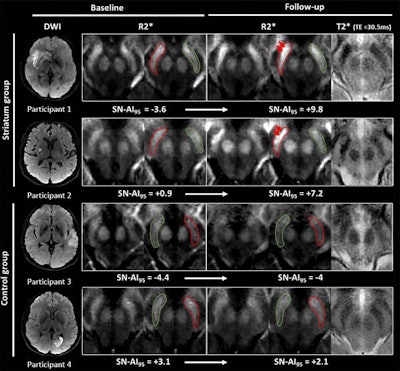

MR images show examples of visual R2* modifications within substantia nigra at baseline (24-72 hours after stroke) and at one-year follow-up in striatum (participants 1 and 2) and control groups (participants 3 and 4). Axial R2* maps are enlarged at mesencephalon level and one of the individual T2* echoes also is shown at follow-up. The substantia nigra is segmented in red ipsilateral to infarct and in green contralateral to infarct. Images without outlines are also shown. Brighter R2* spots are noted with red arrows. Asymmetry index of 95th percentile of R2* within substantia nigra (SN-AI95) measured in these participants is indicated for reference. Participants 1 and 2 show marked asymmetry of R2* within ipsilateral substantia nigra at follow-up, compared with baseline after infarct involving entire striatum (participant 1) or limited to putamen (participant 2). Asymmetry also is visible on individual T2* echo at follow-up. Conversely, no asymmetry was observed in participants 3 and 4 sparing striatum. Images courtesy of Radiology.Linck and colleagues also observed an association between high iron content and poor long-term physical outcomes for stroke patients, particularly when increased iron levels were found on the same side of the brain where the infarction occurred. For example, follow-up tests showed reduced performances of patients when they tried to use their nondominant arms and in a 10-mile walking test.